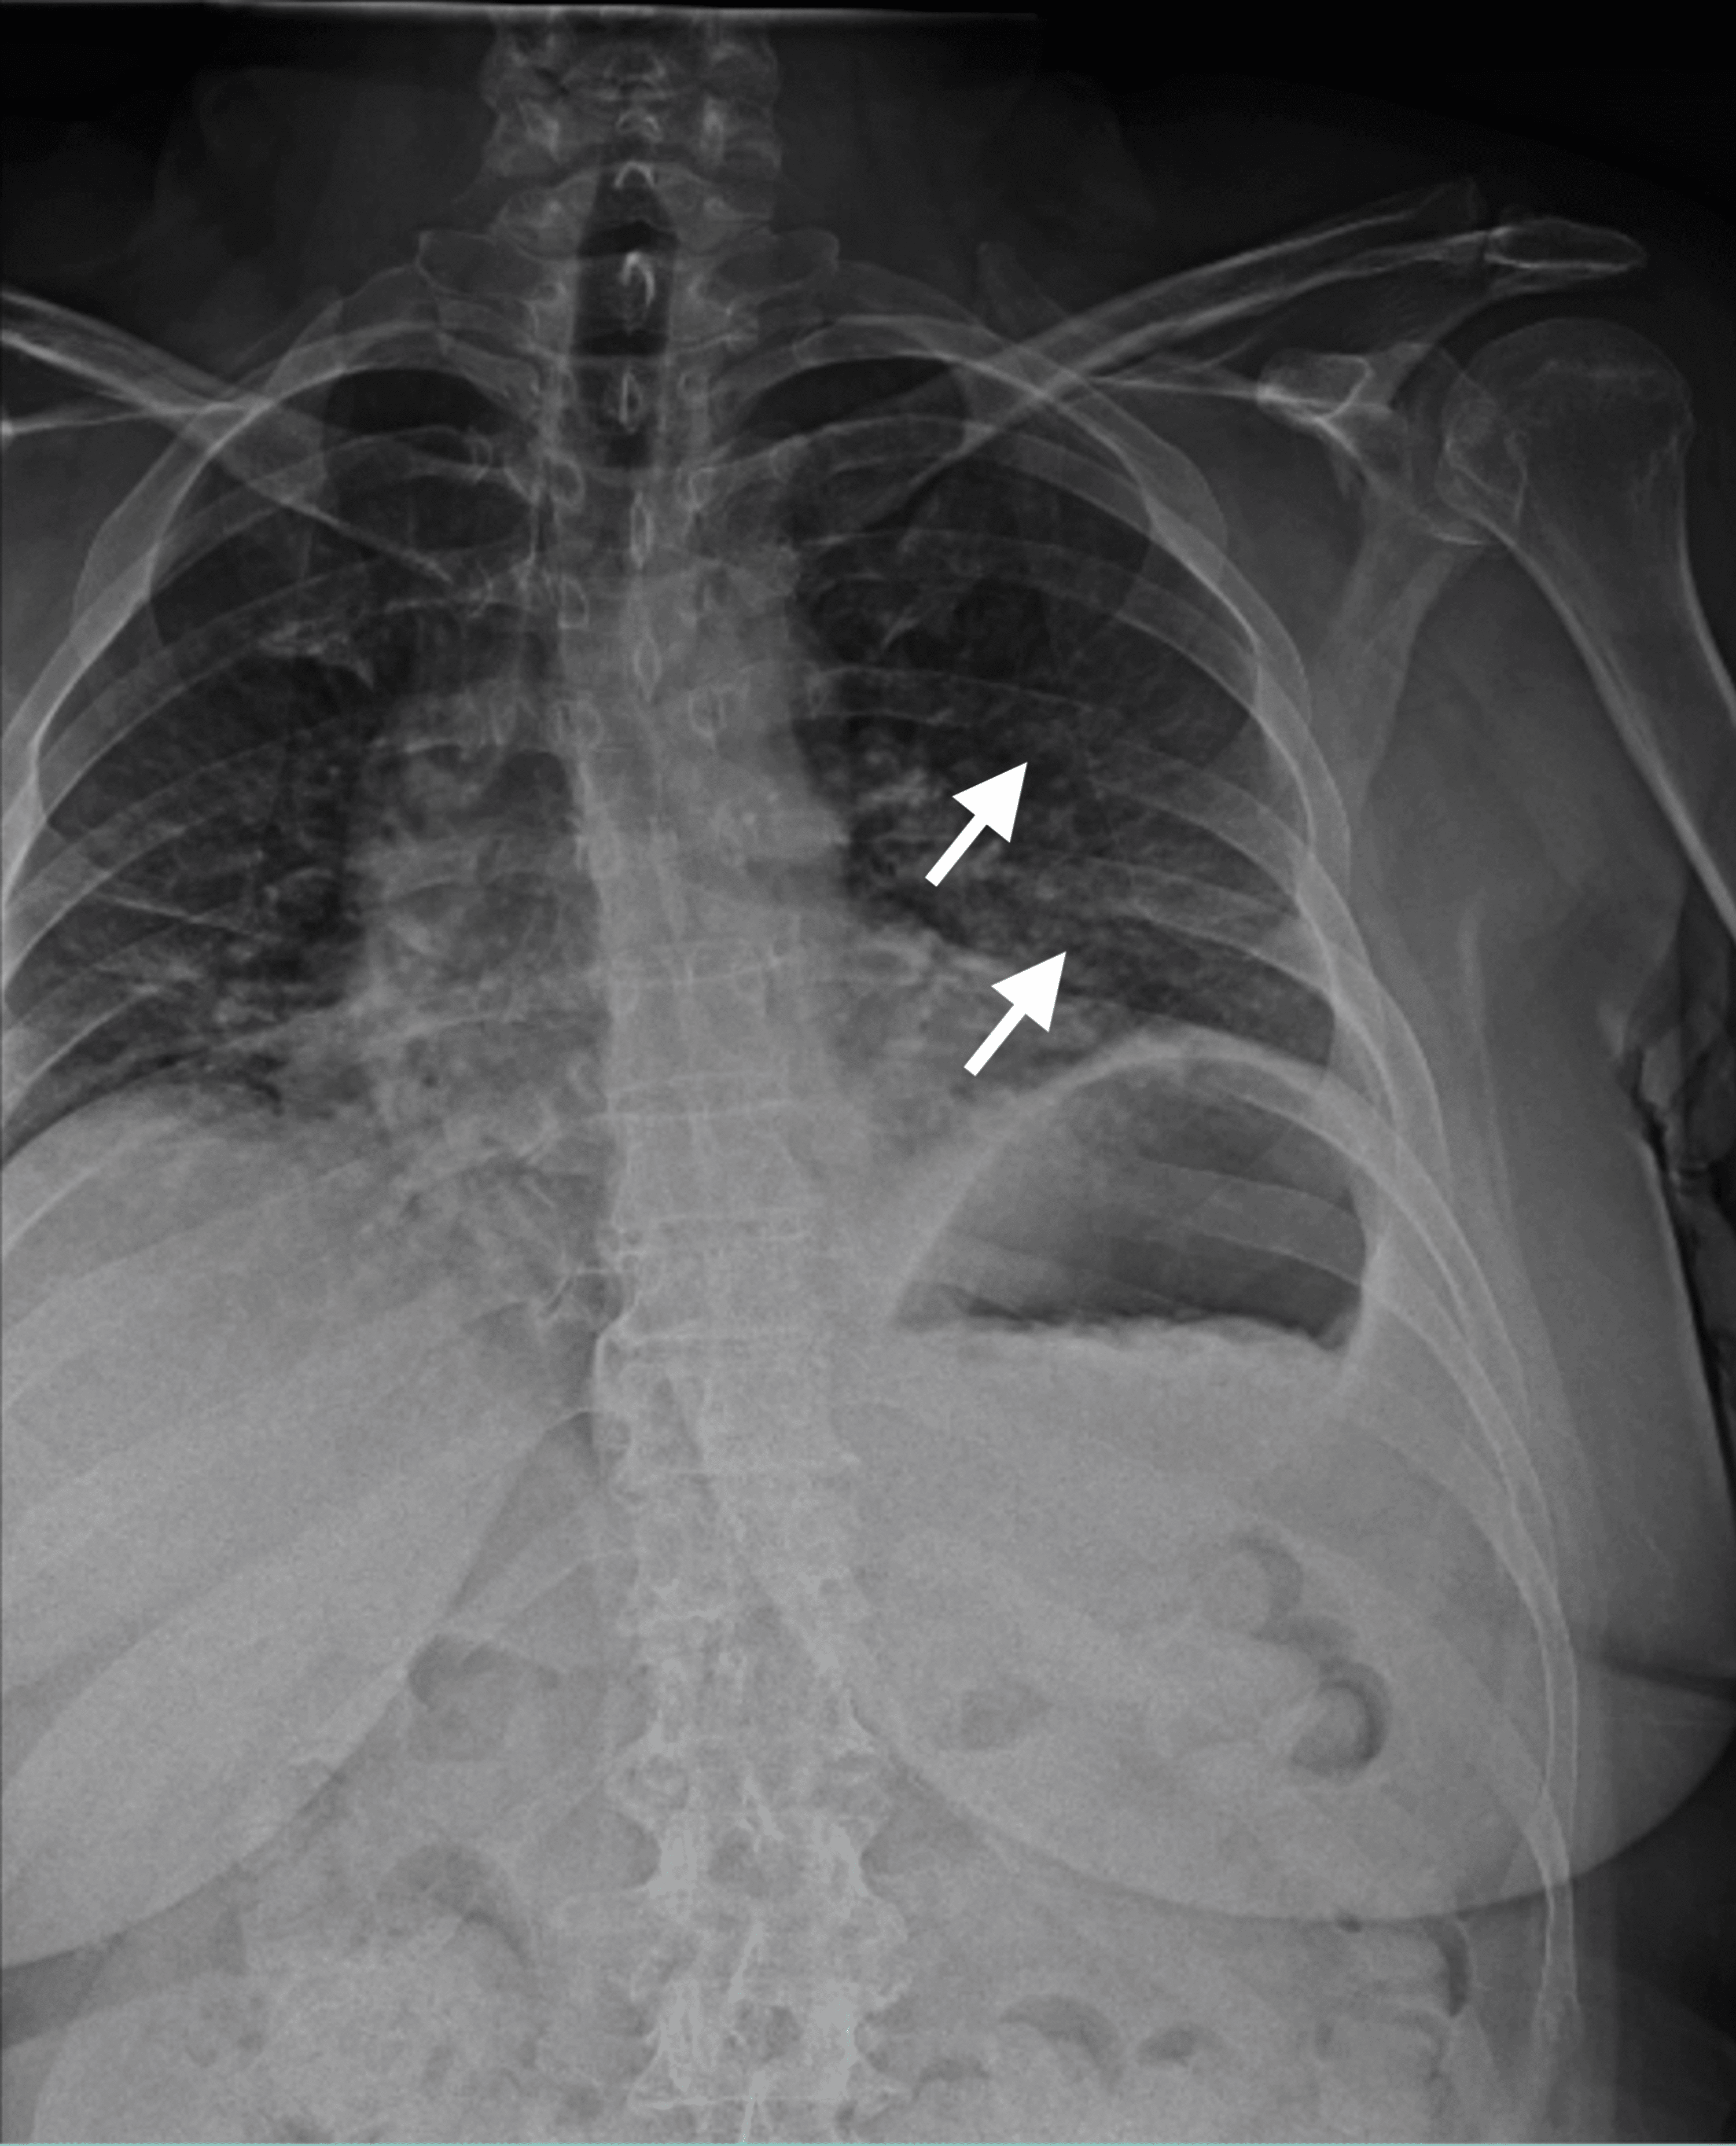

Flail chest with subsequent internal fixation of rib fractures Image Rib Fracture Fixation learn about the indications, techniques, and outcomes of surgical rib fixation for patients with flail chest or non. learn about the causes, symptoms, diagnosis, and treatment of rib fractures, which are common injuries. surgical fixation of complex rib fractures improves outcomes in selected patient groups. Indications for surgical fixation of rib fractures include flail chest,. Chest computed. Rib Fracture Fixation.

chest Xray after rib fixation. Download Scientific Diagram Rib Fracture Fixation this article reviews the pathophysiology, morbidity, mortality and scoring systems of rib fractures, and the role of analgesia and surgery in their treatment. Indications for surgical fixation of rib fractures include flail chest,. learn about the causes, symptoms, diagnosis, and treatment of rib fractures, which are common injuries. Determination of indications and the order. surgical fixation of. Rib Fracture Fixation.